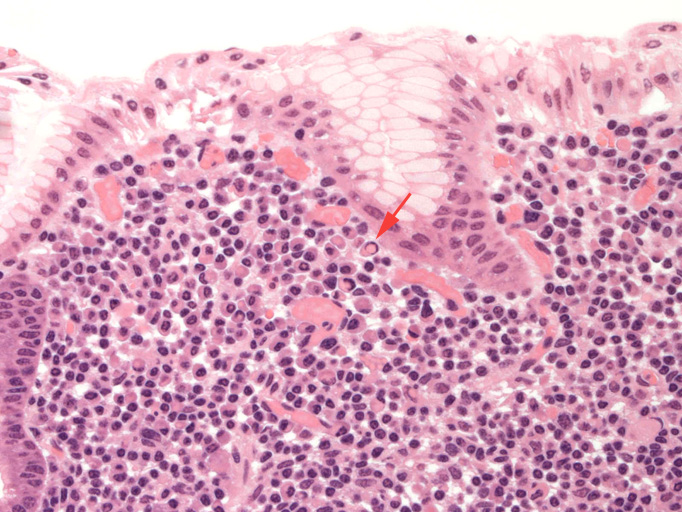

Fig.1と2では粘膜表層でMALT lymphoma腫瘍細胞がplasma cellへ分化している。orangeの矢印で示した核内封入体(Dutcher body)は異型plasma cellの特徴的所見である。その他の多くのplasma cellも核の多型やhyperchromatismを示している。 Fig.3には青矢印でLEL(=lymphepithelial lesion)を示す。MALT lymphoma腫瘍リンパ球の浸潤により胃腺窩が破壊されている。orange矢印はDutcher bodyの様です。

Fig.1 DutcherbodyFig.2 Dutcherbodyその2Fig.3 LEL(青矢印)とDutcherbody(オレンジ矢印)